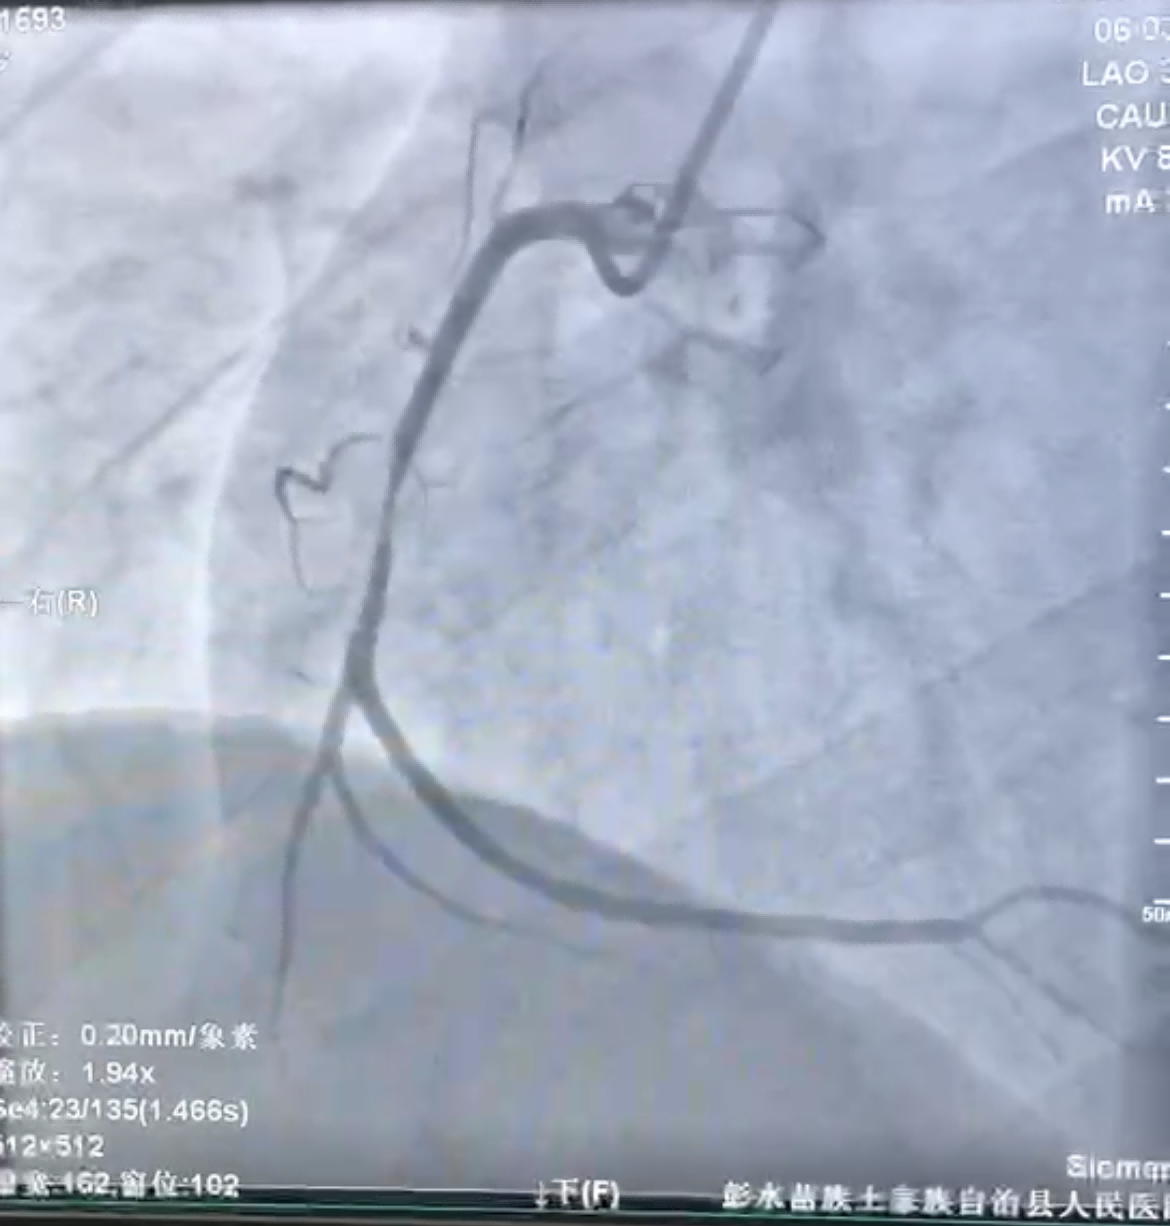

47岁的谢先生因胸痛半月,再发加重3小时,到河豚直播体育app就诊,急诊科张波医师立即行心电图等检查后,考虑急性心肌梗死,经心内科吴玉兰主治医师会诊后立即启动胸痛中心绿色通道,与患者及家属沟通后行急诊冠状动脉介入治疗。通过冠脉造影检查,患者右冠中段次全闭塞,可见血栓影(见图1)。

(图1)